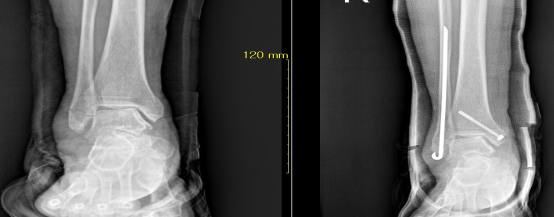

골절 및 탈구시에는 일반 방사선 촬영으로 확진하며 단순골절과 탈구의 경우에는 비수술적 치료방법으로 골절부위를 도수정복 후 석고 고정으로 치유할 수 있습니다. 그러나 도수정복 후에도 골절 부위가 이탈시 부전유합으로 진행되어 추후 어린이는 성장장애 및 외상 후 관절증을 유발시켜 장해에 이르기에 부득이 수술적 방법을 고려합니다. 본원은 최신식 이동형 C-ARM 영상장치를 이용하여 골절부위를 실시간으로 촬영하여 수술을 시행하고 있습니다.